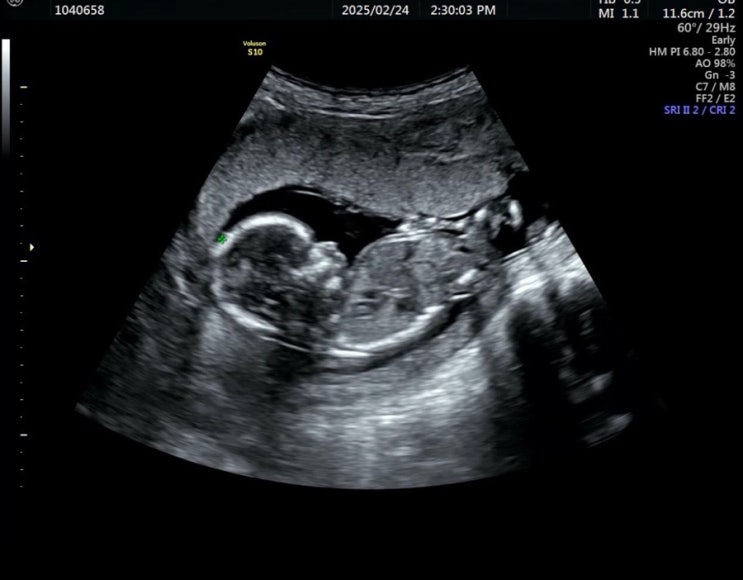

[임신일기] 15. 1차 기형아 검사 - 임신 12주 2일

임신 12주차에 진행했던 1차 기형아 검사 임신 12주 2일 너무 지나고 기록이라 자세한 치수는 기억나지 않...